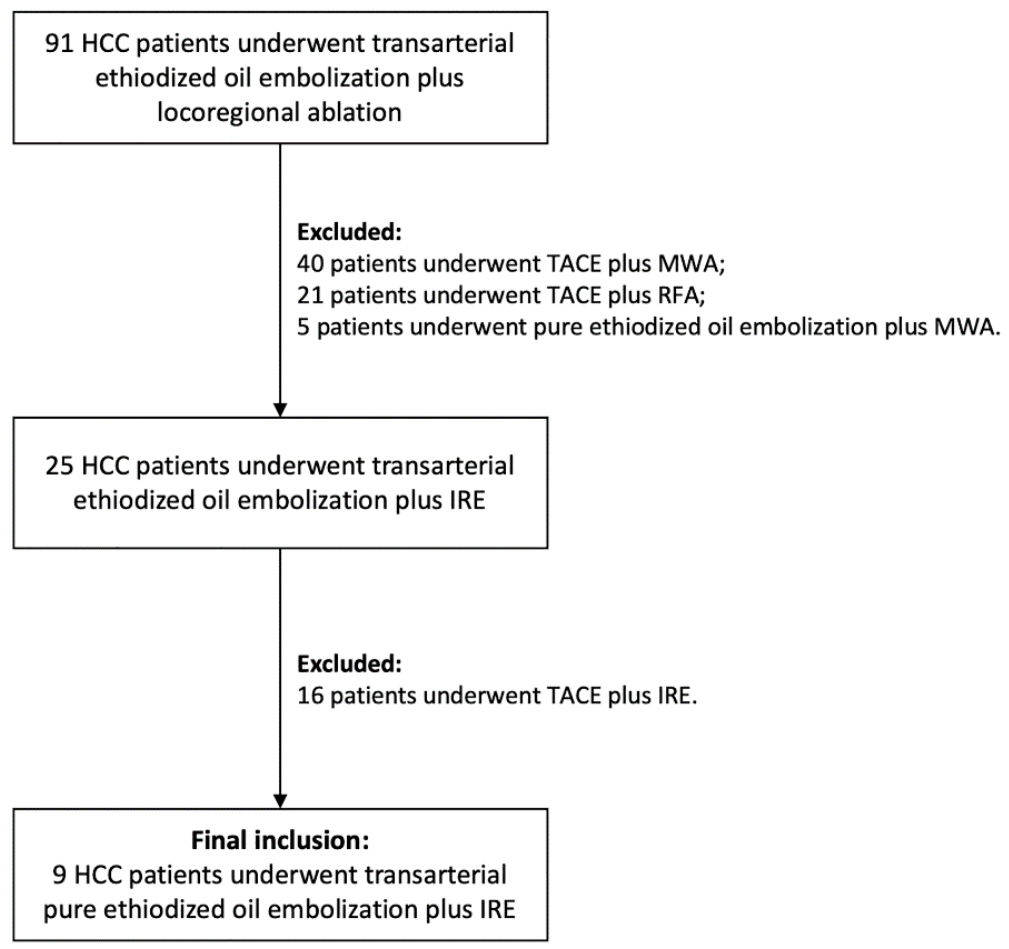

2. Materials and Methods

2.1. Treatment Strategy and Inclusion Criteria

3. Results

3.1. Patient Collective and Target-HCC Characteristics